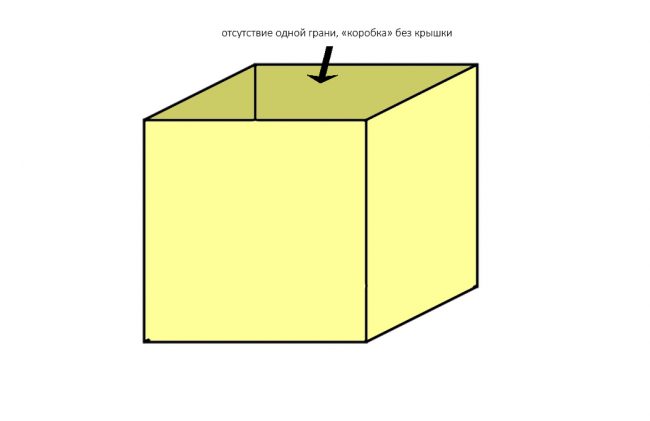

Любые костные дефекты челюстей мы можем представить в виде шестигранника (гексаэдра) или, если хотите, в виде куба:

По отсутствию одной или нескольких граней мы можем легко их классифицировать.

Например, отсутствие одной костной стенки характерно для полостей после цистэктомии:

или лунок зубов:

и т. д.

Отсутствие двух стенок — «классика жанра»:

к ней относятся большинство видов атрофии при длительном отсутствии зубов:

Ну и, отсутствие трех стенок характерно для значительных дефектов кости:

например, для седловидных или т. н. «вертикальных» дефектов:

И крайняя степень — отсутствие четырёх или пяти стенок:

ставит под сомнение целесообразность проведения остеопластики, поскольку добиться качественного результата в таких случаях крайне сложно:

но вполне возможно:

Сопоставив понятие периметра с тем, что мы теперь знаем об остеогенезе, легко объяснить, почему при проведении синуслифтинга, в принципе, можно использовать биоматериалы без добавления аутокостной стружки:

Мы имеем дефект с сохранением пяти стенок из шести, с большой площадью поверхности и относительно небольшим расстоянием до центра:

где миграция клеток и васкуляризация идет от периметра к центру со всех сторон и предел роста как таковой, в принципе отсутствует.

И наоборот, такой же по объему дефект, но не имеющий двух или трех стенок, «чистым» биоматериалом, практически, не вытянуть, поэтому мы должны (нет, обязаны!) добавлять в ксенографт аутокостную стружку:

что, как я уже писал, увеличивает предел роста:

И дает возможность получить нормальный результат остеопластики почти в любом объеме.

выбор метода остеопластики зависит не столько от объема, сколько от формы дефекта, наличия у него костных стенок и биотипа принимающего ложа. Чем больше расстояние от периметра до геометрического центра графта, тем больше аутокостной стружки требуется ввести в графт для его успешной регенерации.